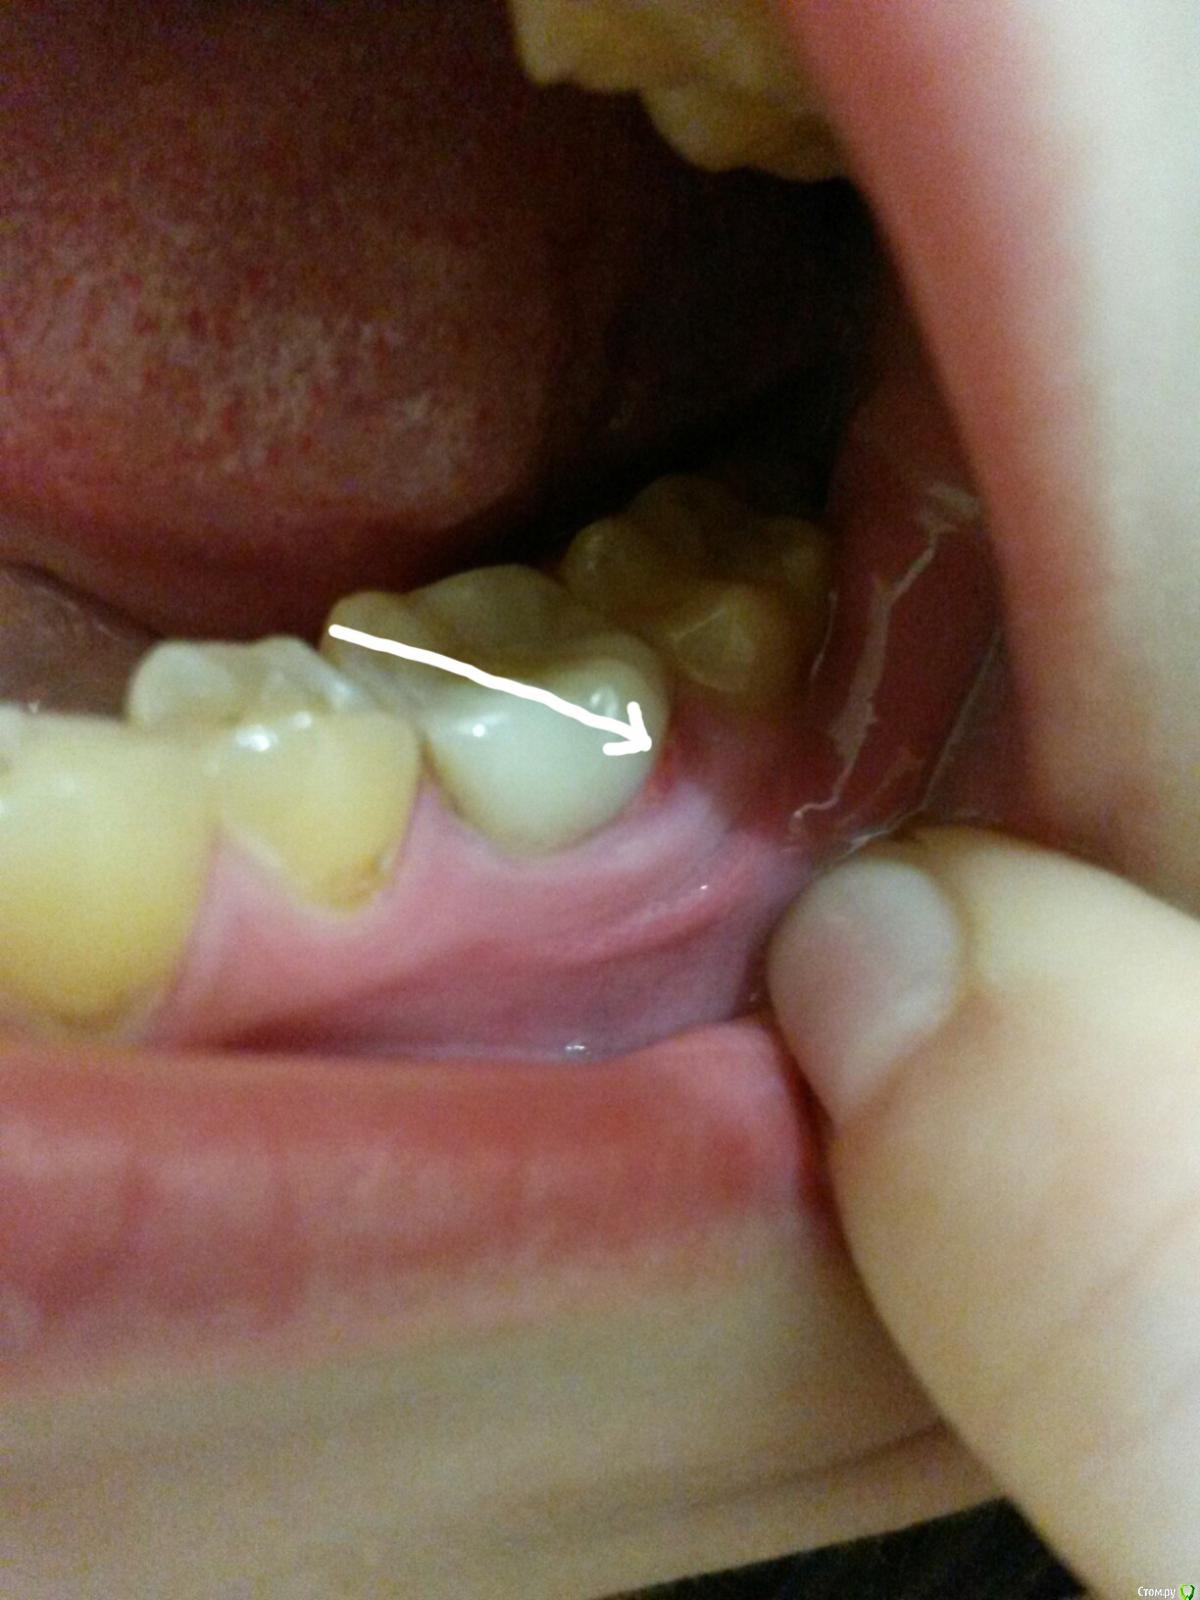

Melancholia Опубликовано 19 февраля, 2018 Автор Поделиться Опубликовано 19 февраля, 2018 В итоге сходила к парадонтологу, он сказал надо делать уже открытый кюретаж резать десну и выгребать всю инфекцию, т.к. карман глубокий и это красное это грануляционная ткань и костная ткань уже убывает. В общем, если у кого чтото-то похожее не сидите как я и не ждите что десна сама пройдет, если за 4 дня не прошла, то надо идти к пародонтологу хорошему.Вот как выглядит это сейчас. Ссылка на комментарий